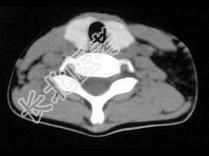

- 单项选择题女,17岁, 发现左侧颈部包块半年余,PE: 病灶质软,境界不清, 无压痛,CT如图所示, 最可能的诊断是 ( )

D、颈部淋巴管瘤